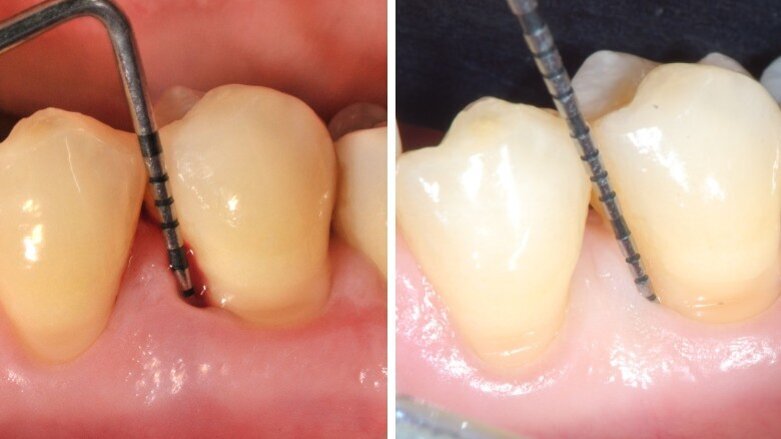

Una congrua igiene domiciliare può influenzare in modo significativo le condizioni di salute orale. È un concetto noto, ma più che mai in questo periodo merita di essere avvalorato. In occasione di ogni congresso/evento, a cui ho avuto l’onore di partecipare, la prima diapositiva, dopo quella introduttiva dell’argomento, con il titolo della presentazione, è quella riprodotta nella figura 1a. Tale diapositiva voleva sottolineare quali erano le premesse e le conclusioni dei concetti illustrati nella conferenza. I fattori più rilevanti, nel determinare il successo di un trattamento odontoiatrico, in particolare di una gestione non chirurgica, in presenza di una infiammazione placca-indotta, sono quelli evidenziati dal cerchio azzurro (Fig. 1a). Certamente l’impegno del clinico in una ri-motivazione continua di ogni soggetto in cura è il principale in ordine di importanza, a seguire una efficace terapia eziologica, che mira a rimuovere professionalmente la noxa patogena, composta da biofilm. La cavità orale umana ospita un complesso microbioma composto da batteri, protisti, archei, funghi e virus1, 2. È dunque ricco di batteri e presenta una componente virale, di cui, proprio al giorno d’oggi, possiamo capirne il potenziale aggressivo. Terzo punto chiave: l’approccio non chirurgico dovrebbe essere sempre la prima fase di trattamento, seguita eventualmente da una gestione chirurgica del caso, se non si sono raggiunti gli obiettivi o una stabilità clinica, che soddisfa le aspettative del paziente e del team odontoiatrico. Tutto ciò che viene elencato nella diapositiva, al di sotto del cerchio azzurro (Fig. 1a), riguarda una serie di apparecchiature, prodotti, sostanze, medicinali, eccetera, che pur trovando indicazioni, sono sempre aggiuntive e mai da utilizzare come monoterapia3.

Frequentemente nelle fasi iniziali di un impegno didattico, presentavo un caso che in primis aveva sorpreso anche me, per la sua evoluzione positiva, ma che mi permetteva di oggettivare quanto rilevante fosse la performance domiciliare del paziente e la sua adesione alle raccomandazioni di igiene orale, fornite in modo sempre personalizzato alle esigenze individuali di ciascuno.